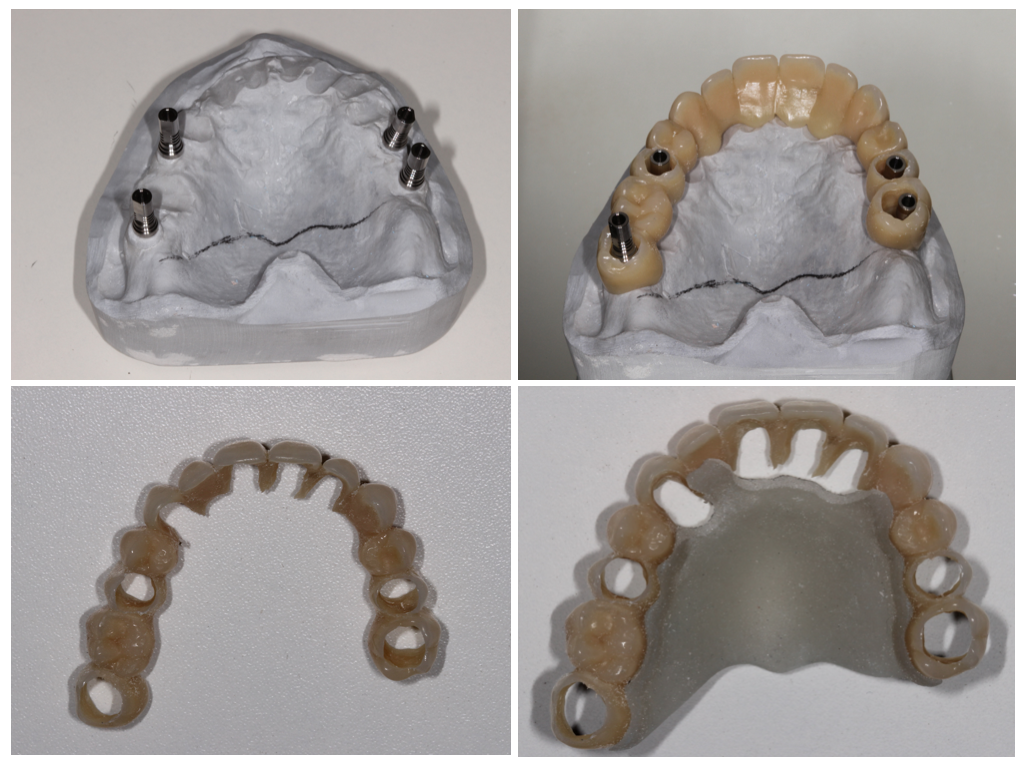

Bridge provisoire transvissé réalisé au laboratoire :

Ce bridge a été réalisé en technique d’impression numérique avec création de la fausse gencive par maquillage de surface